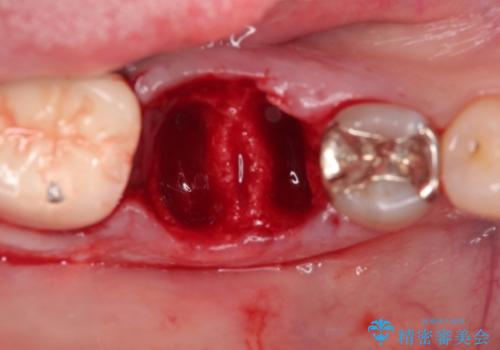

破折の深さが歯根まで及んでいたため抜歯を行いました。

抜歯をしたあと骨が痩せないよう抜歯直後に骨補填材を入れています。

骨が成熟するまで待ち、インプラントを埋入しました。